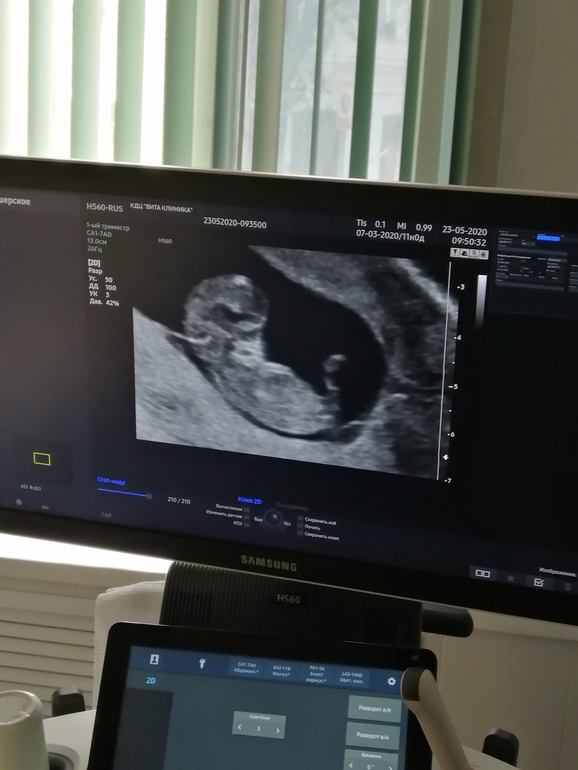

Результаты: УЗИ, КТГ, доплера, скринингаДевчонки всем привет! Вчера вечером не много тянуло живот слева гдя яичник, ну я утром поехала на узи, все посмотрели поставили 11 недель, сказали все хорошо но есть не большая тахикардия плода, сердечко бьётся часто, то поменьше 170,190 ударов, не знаю, и не большой тонус по задней стенке, прикрепление тоже по задней стенке,малыш сказали очень активный, видела как шевелил ручками и ножками🤗 сегодня вроде ни чего, пью ношпу, на ночь папаверин, на прием во вторник, но все равно переживаю из за тахикардии😕